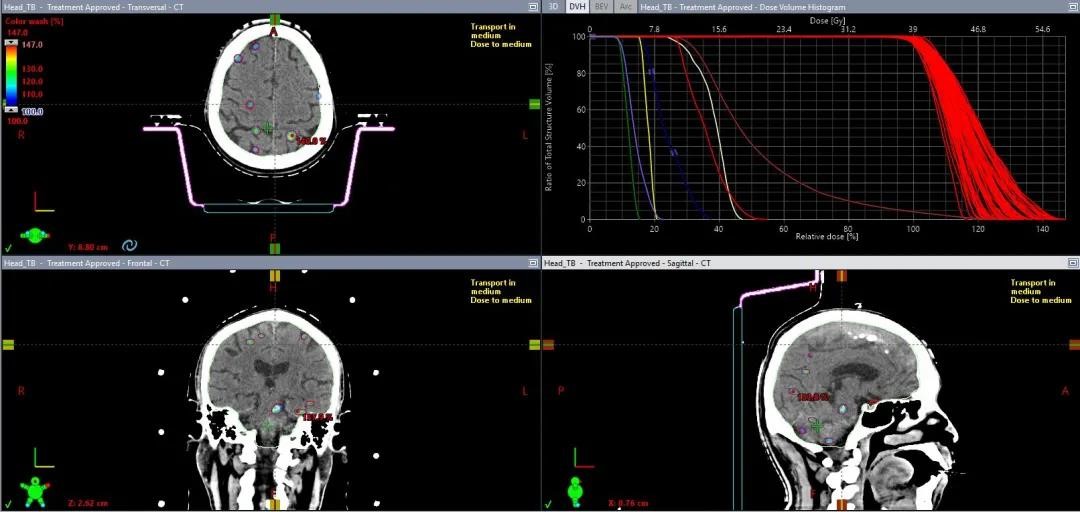

03 超多发脑转移

67个Mets,39Gy/13F,全脑平均剂量17Gy,

明显低于全脑照射,而且病灶可以给到更高剂量

67个靶点,每个都能达到处方覆盖要求

使用HyperArc一键式完成67个靶点治疗只要10分钟